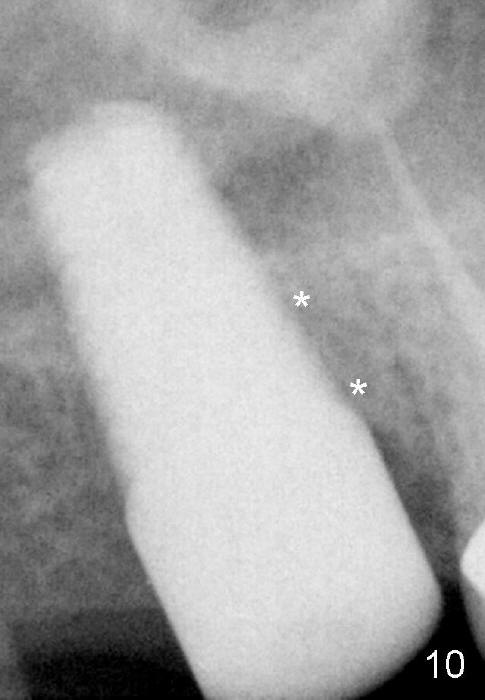

Fig.10 (5.5 months postop) * mesial socket space disappears (filled by new bone).